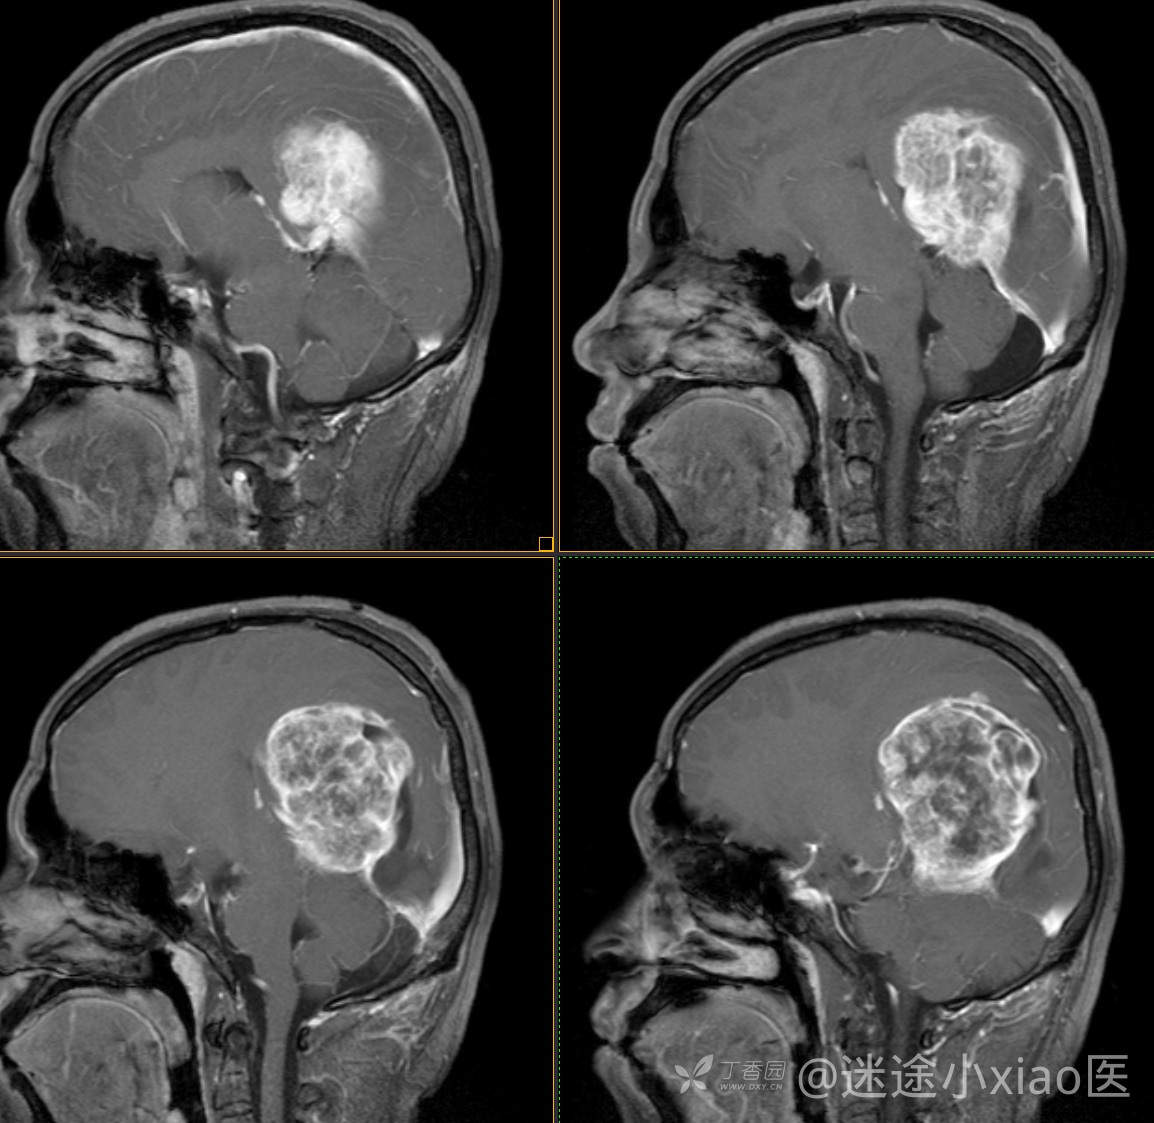

患者年龄:43

患者性别:男

简要病史:头痛3月余,查体无殊